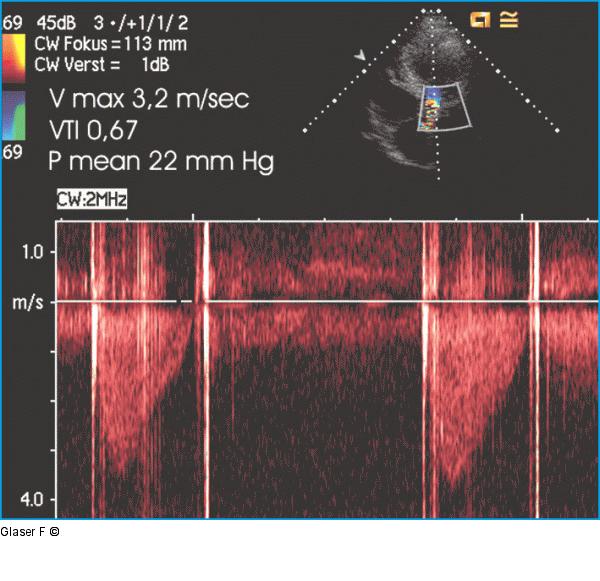

Abbildung 5: CW-Doppler CW-Doppler der Aortenklappenprothese: hohe Maximalgeschwindigkeit, relativ hoher mittlerer Gradient trotz reduzierter linksventrikulärer Pumpfunktion. |

CW-Doppler der Aortenklappenprothese: hohe Maximalgeschwindigkeit, relativ hoher mittlerer Gradient trotz reduzierter linksventrikulärer Pumpfunktion. |